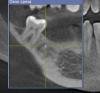

nemorr Опубликовано 9 сентября, 2013 Автор Поделиться Опубликовано 9 сентября, 2013 (изменено) @nemorr, Выложите скриншоты, ответы будут быстрее..Там просто глубину настраивать нужно (там можно любую посмотреть) Беда в том что я не знаю какую нужно глубину ставить. Но я сделал скриншоты, общий на глубине по умолчанию. И 2 маленьких на разной глубине кости орентировался на максимально видимую дырку от зуба. И сразу второй вопрос по снимку.Вот старое (начало этого года) сложно удаление где мне зуб в кости третью ветвь тройничного нерва защемил. Было два удаления, почему не могу сказать точно, врач говорил мол зуб ретинированный, а может просто не увидел всё кто знает.В обще я контрольный снимок уже делал этого места там пусто, но вот сейчас на 3d что там за белая точка? Изменено 9 сентября, 2013 пользователем nemorr Ссылка на комментарий